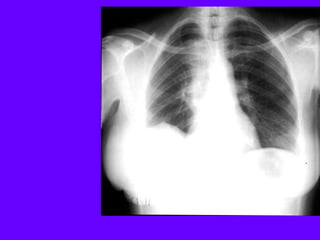

A 27-year-old man is referred to you for evaluation of an

abnormal chest radiograph. About 5 months ago, he consulted

a doctor because of excessive thirst. Evaluation resulted in the

diagnosis of diabetes insipidus, which responded favorably to

desmopressin administered nasally. Recently, he started to

notice shortness of breath when climbing stairs, and a chest

radiograph was obtained.

•Patient history reveals significant tobacco smoking, up to two

packs daily, for at least 14 years. The patient noticed the

shortness of breath for at least 2 years, and recently, he noted

a point of tenderness over the chest wall, lateral to the

posterior axillary line on the left.

•Oxygen saturation is 94% while breathing room air, and the

rest of his vital signs were normal. Auscultation reveals only

rare crackles without prolongation of the expiratory phase.

There is a point of tenderness over the left sixth and seventh

ribs in the posterior axillary line, and a chest CT scan is

obtained.

The most likely diagnosis is:

A. Metastatic tumor of unknown primary

site.

B. Sarcoidosis.

C. Langerhans cell histiocytosis.

D. Idiopathic pulmonary fibrosis.